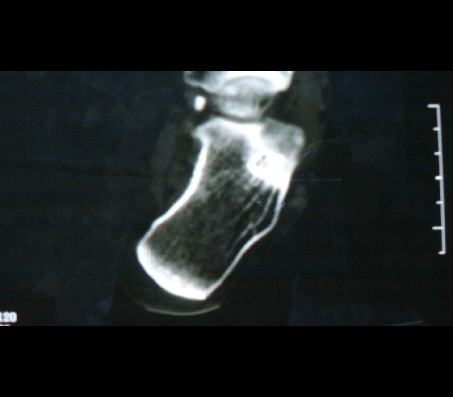

1致密骨岛;2跟骨骨髓窦。

高密度是骨岛。2跟骨骨随窦。

考虑为:1)跟骨骨髓窦。2)致密骨岛。